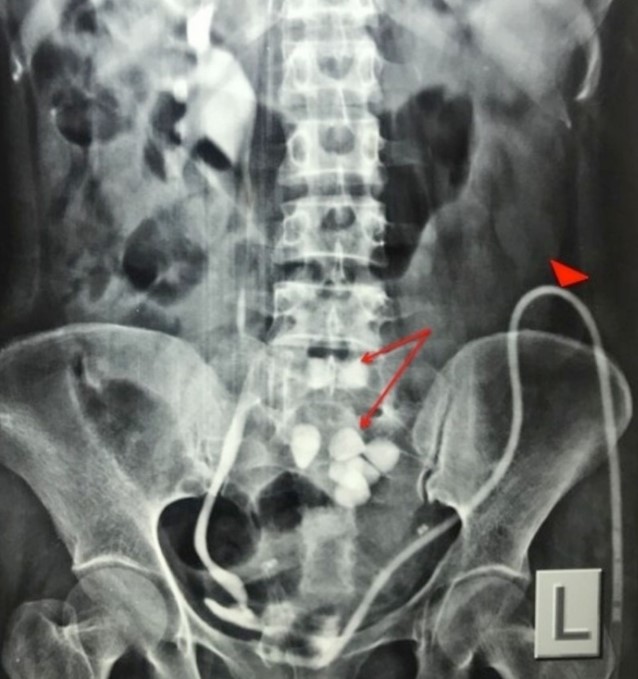

Tests done to investigate prostatic disorders may include, but are not limited to the following: urinalysis; intravenous urography; uroflowmetry; cystourethrography; and determination of the prostate-specific antigen (PSA) values. In addition, tests to evaluate creatinine levels, blood urea nitrogen (BUN), and phosphate and calcium levels may be done to determine if metastasis to the bone has occurred. Other diagnostic measures may include: prostatic biopsy; ultrasound; magnetic resonance imaging (MRI); and computed tomography (CT) scan.